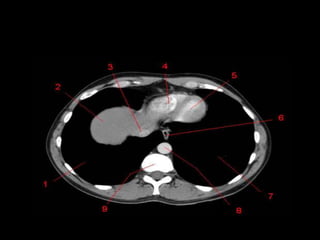

Mediastino • 1: vasosbraquiocefálicos direitos. • 2: aorta ascendente e veia cava superior superpostas. • 3: átrio direito. • 4: veia cava inferior. • 5: vasos braquiocefálicos esquerdos. • 6: arco aórtico. • 7: tronco pulmonar. • 8: apêndice atrial esquerdo. • 9: ventrículo esquerdo